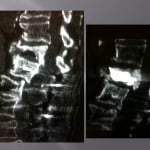

Vertebroplasty in the case of an intra-spongy hernia symptomatic hyperalgic.

This situation can occur when a collapse of the spongy bone holding the upper disc and able to provoke a large bone edema under chondral tissues. The principle of the vertebroplasty consists in consolidating the portion of the bone below the intra spongy hernia. The indication and the results of the consolidation of the vertebrae in this kind of bone damage has already been published (simonetti European Radiology) and showed a significant enhancement of the analog pain scale at the first day.

The vertebroplasty technique in this context can present a unique difficulty: the precision of positioning of the cement adjacent to the hernia with intra-discal passage. The scannographic volume acquisition determines in a first step the ideal path for the distal end of the trocar is located under the median portion of the hernia. The filling of the spongy bone is performed with a viscous cement which will fill the whole lower part to the hernia. The injection will be performed under continuous scopy and will avoid any disc passage. The rotation motions of the cannula bevel of the trocar can be very useful to better spread the cement.